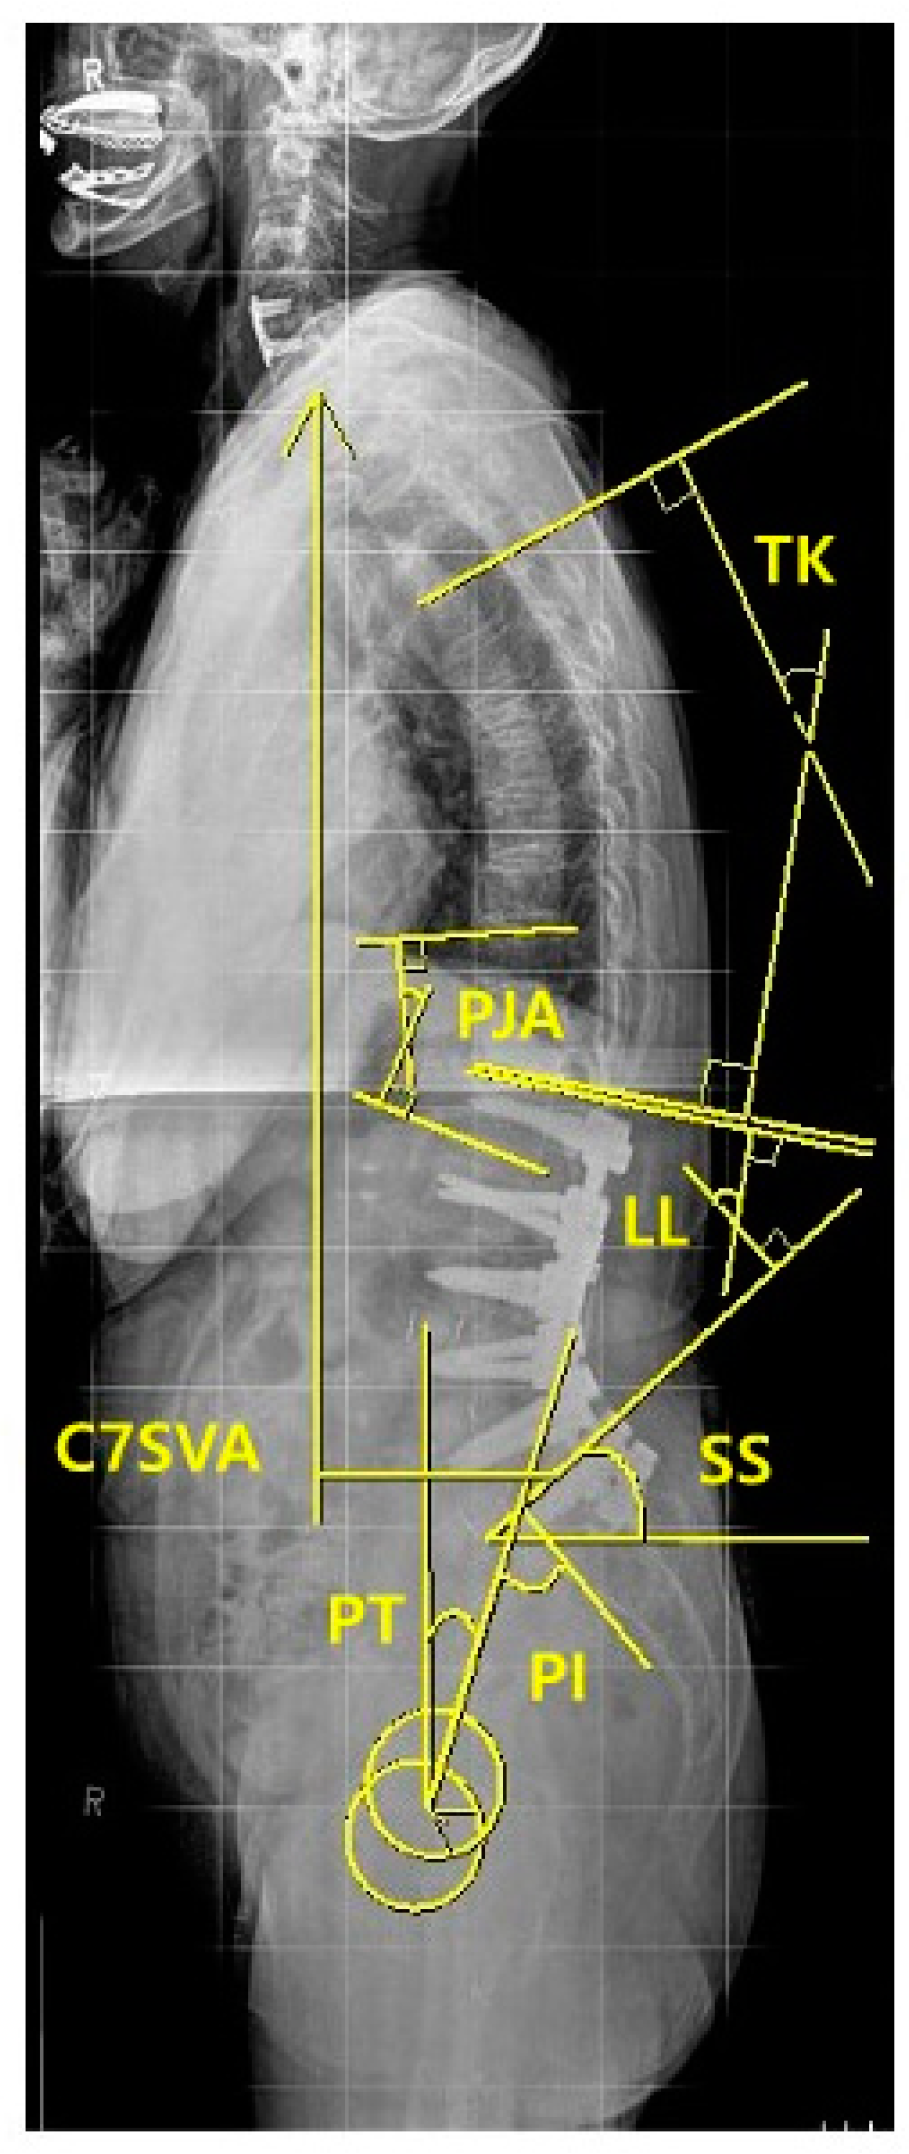

The following demographic and surgical data were collected: age at surgery ; sex (female/male); bone mineral density (BMD, T-score); body mass index (BMI, kg/m2); smoking; previous spinal fusion; American Society of Anesthesiologist physical status (ASA) grading; iliac fixation; disc degeneration by Pfirrmann grade [16] at T12-L1 segment (1,2,3: mild to moderate; 4,5: severe); muscularity status at T12-L1 (cross-sectional area [CSA], cm2) and fat infiltration grade (mild to moderate, if <50%; severe, if ≥ 50%) in erector spinae muscle at T12-L1 in T2-weighted axial magnetic resonance (MR) images using Picture Archiving and Communication System (PACS) by Philips ACHIEVA 3.0T (Philips Healthcare, UK) and the ImageJ software. The region of interest (ROI) for erector spinae muscle at T12-L1 level was outlined polygonally with manipulation of graphic cursor and handled with pseudocoloring method.[17] (Figure 1) Then, CSA (Figure 1A) were calculated and fat infiltration grade (Figure 1B) was determined.

For radiographic assessment of spinopelvic parameters, standing 36-inch-long cassette AP and lateral radiographs of the whole spine were measured at the preoperative, the immediate postoperative, and the regular postoperative outpatient visits (3, 6, 9 months, 1-, 2-year and the final follow-up), respectively. On the radiographs, C7 sagittal vertical axis (C7SVA), thoracic kyphosis (TK) [18], thoracolumbar kyphosis (TLK) [18,19], lumbar lordosis (LL) [18], sacral slope (SS) [18], pelvic tilt (PT) [18], pelvic incidence (PI) [18,19,20] and proximal junctional angle (PJA) were measured (Figure 2). We also collected and analyzed the change (preoperative minus postoperative) of each radiographic parameter between the preoperative and the immediate (3 months) postoperative.

Figure 2. Methods for measuring A) CSA and B) FI of erector spinae muscle.